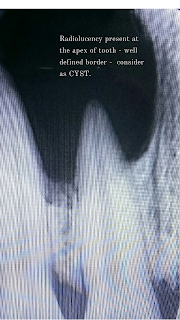

4. An x-ray (radiograph) needs to be taken. This is to confirm the size of the abscess and occasionally can be used in adjunction with the above tests to make the diagnosis. It is also useful to see the underlying cause of the abscess if this is not obvious clinically.